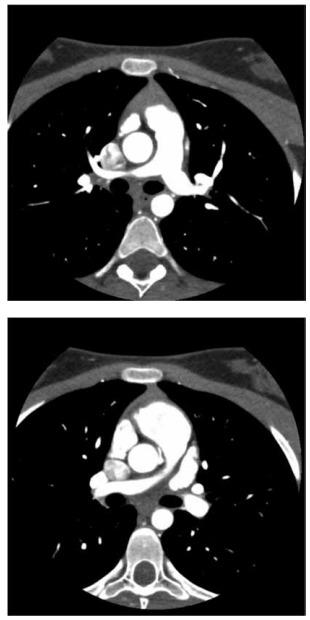

Paciente de 1 mês de idade foi admitido em Unidade de

Terapia Intensiva, acompanhada de cuidadora de abrigo,

devido à piora da cianose. Mãe drogadita perdeu guarda

dos 6 filhos. A saturação na Unidade manteve-se estável,

ao redor de 84%, sem insuficiência cardíaca congestiva,

em uso de propranolol; foi acompanhado no ambulatório

até os 2 anos de idade e realizada intervenção cirúrgica

cardíaca. Com base nos seguintes exames complementares, quais seriam, sucessivamente, a cardiopatia congênita provável, a cirurgia realizada aos 2 anos de idade

e a cirurgia atual para a qual foi convocada?

(Arquivo pessoal; imagens usadas com autorização)